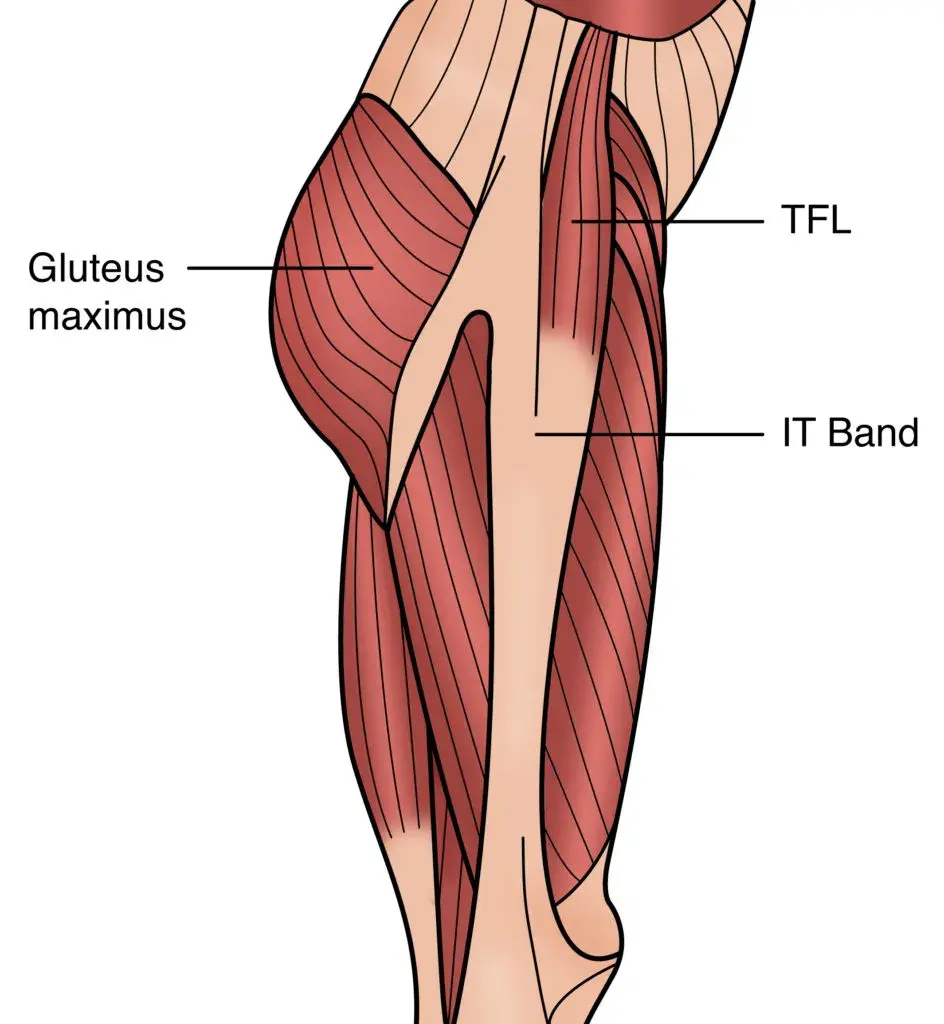

阔筋膜张肌,比你想象的更复杂

阔筋膜张肌(TFL)作为一块髋部肌肉为很多手法治疗师所熟悉。它在下肢,骨盆和脊柱的疼痛和功能障碍中扮演重要角色。但我们却知之甚少,因为关于这块肌肉的临床研究非常之有限。此外,大部分关于TFL以及与之相连的髂胫束(ITB)的解剖研究和观点都过于简单化了。因为内容较为,本期关于阔筋膜张肌的讨论将分为两期,第一期(本期)主要是介绍其解剖和功能,第二期将重点介绍针对阔筋膜张肌的松解术和相关练习。

阔筋膜张肌和髂胫束相连,其解剖分布颇为复杂。它扮演着多种功能,不仅参与髋关节运动而且也通过阔筋膜(fascia latae)和ITB起到加强筋膜张力的作用。因此,TFL不仅能维持单腿站立时的姿势,而且还能避免因体重,地面冲击力以及两者形成的合力对股骨造成的拉伸应力(Tensile stress)。

讨论TFL的解剖离不开髂胫束。Pare等(1981)发表了可以说是迄今为止有关TFL最全面的解剖学和肌电学研究。在此之前,Kaplan在1958年提出了一项关于阔筋膜张肌和髂胫束的详尽研究2。

一般认为,TFL起自髂嵴,始于髂前上棘(具体位置位于缝匠肌起点的外侧)并随髂嵴往后延伸约2-5公分并整合入臀部筋膜(gluteal fascia)6,7,8。Pare等(1981)指出TFL实际上有两个功能意义和解剖意义都互不相同的起点,即内前(anteromedial, AM)起点和侧后(posterolateral)起点。我们会在后面详细讨论。

TFL位于髋关节前侧,就像三明治一样被浅层和深层的中间纵向层所包绕。另外,中间纵向层也有纤维直接和臀大肌的浅层纤维相融合。因此,中间纵向层部分融入臀大肌,也有部分融入TFL。